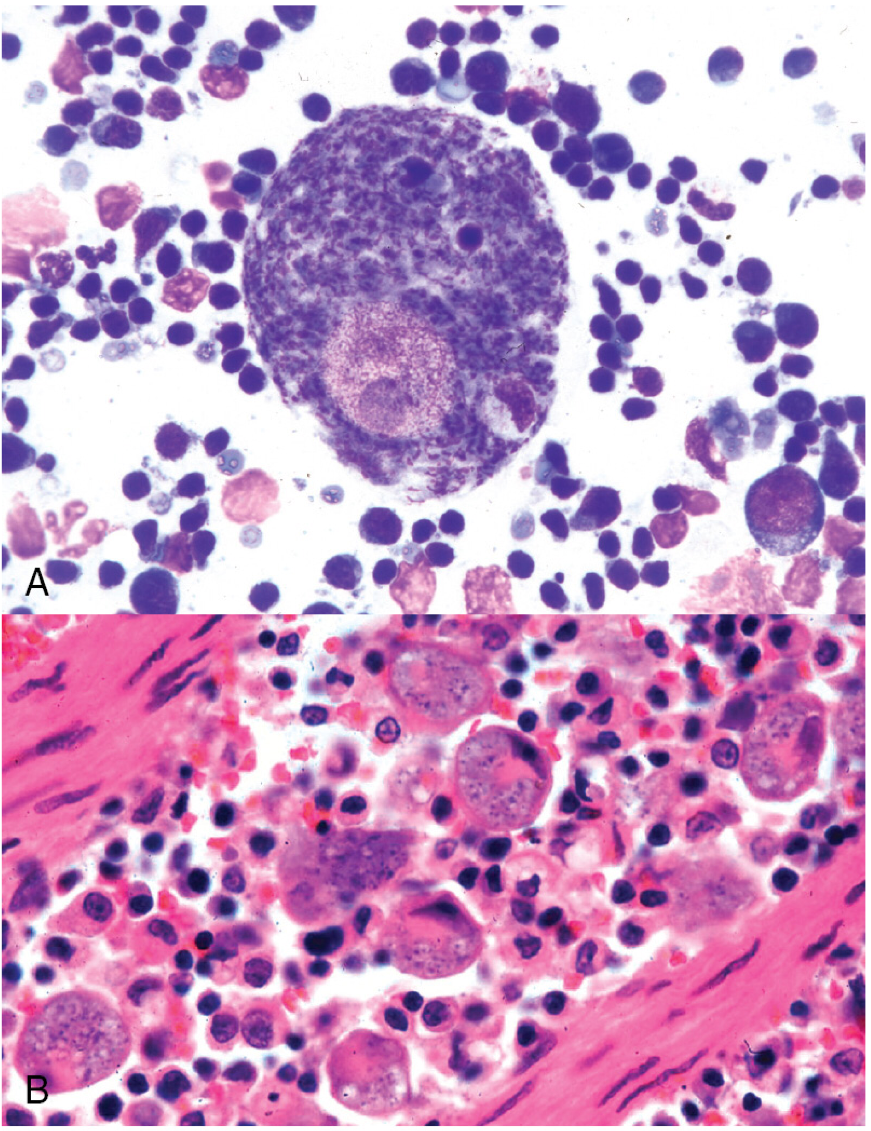

Tissue aspirates from a necropsy of a cat in Missouri show large macrophages filled with schizonts. What was the likely cause of death?

Occlusion of the vessels of the lungs, brain, liver, LN, and spleen.

*The protozoal parasite is Cytauxzoon felis. In the schizogenous phase, marcophages become very large after phagocytosing schizonts and will occlude vessels. In the erythrocytic phase, anemia results.